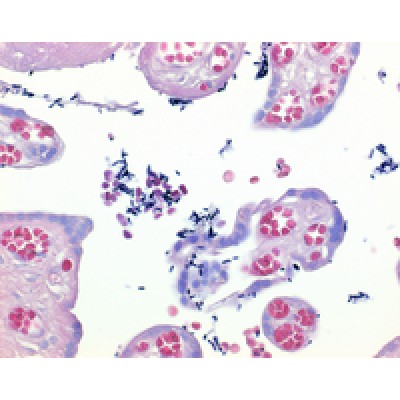

solução de Lugol estabilizada com PVP - para o método de coloração de Gram. "A solução de Lugol é utilizada para o diagnóstico de células humanas ou investigação citológico de amostra de origem humana.